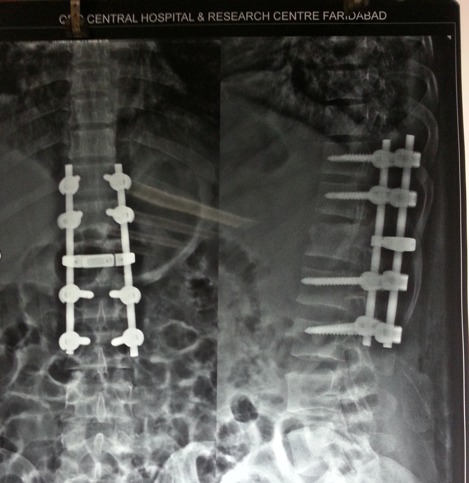

X-ray After Surgery

Dorsolumbar spine Fixation.